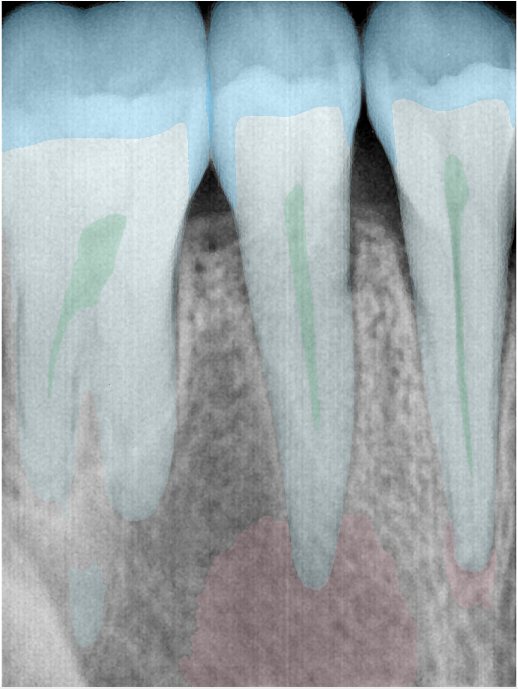

CR/DR 牙齿分割阶段记录

当前进展

- 完成了 CR/DR 牙齿相关分割训练

- 当前结果已经达到阶段预期,但仍有细节问题需要继续处理

相关测试

遇到的问题

- 训练过程中出现过 mask 下移问题

- 部分结果会出现 box 填充异常

- mask 边缘仍然有比较明显的锯齿感